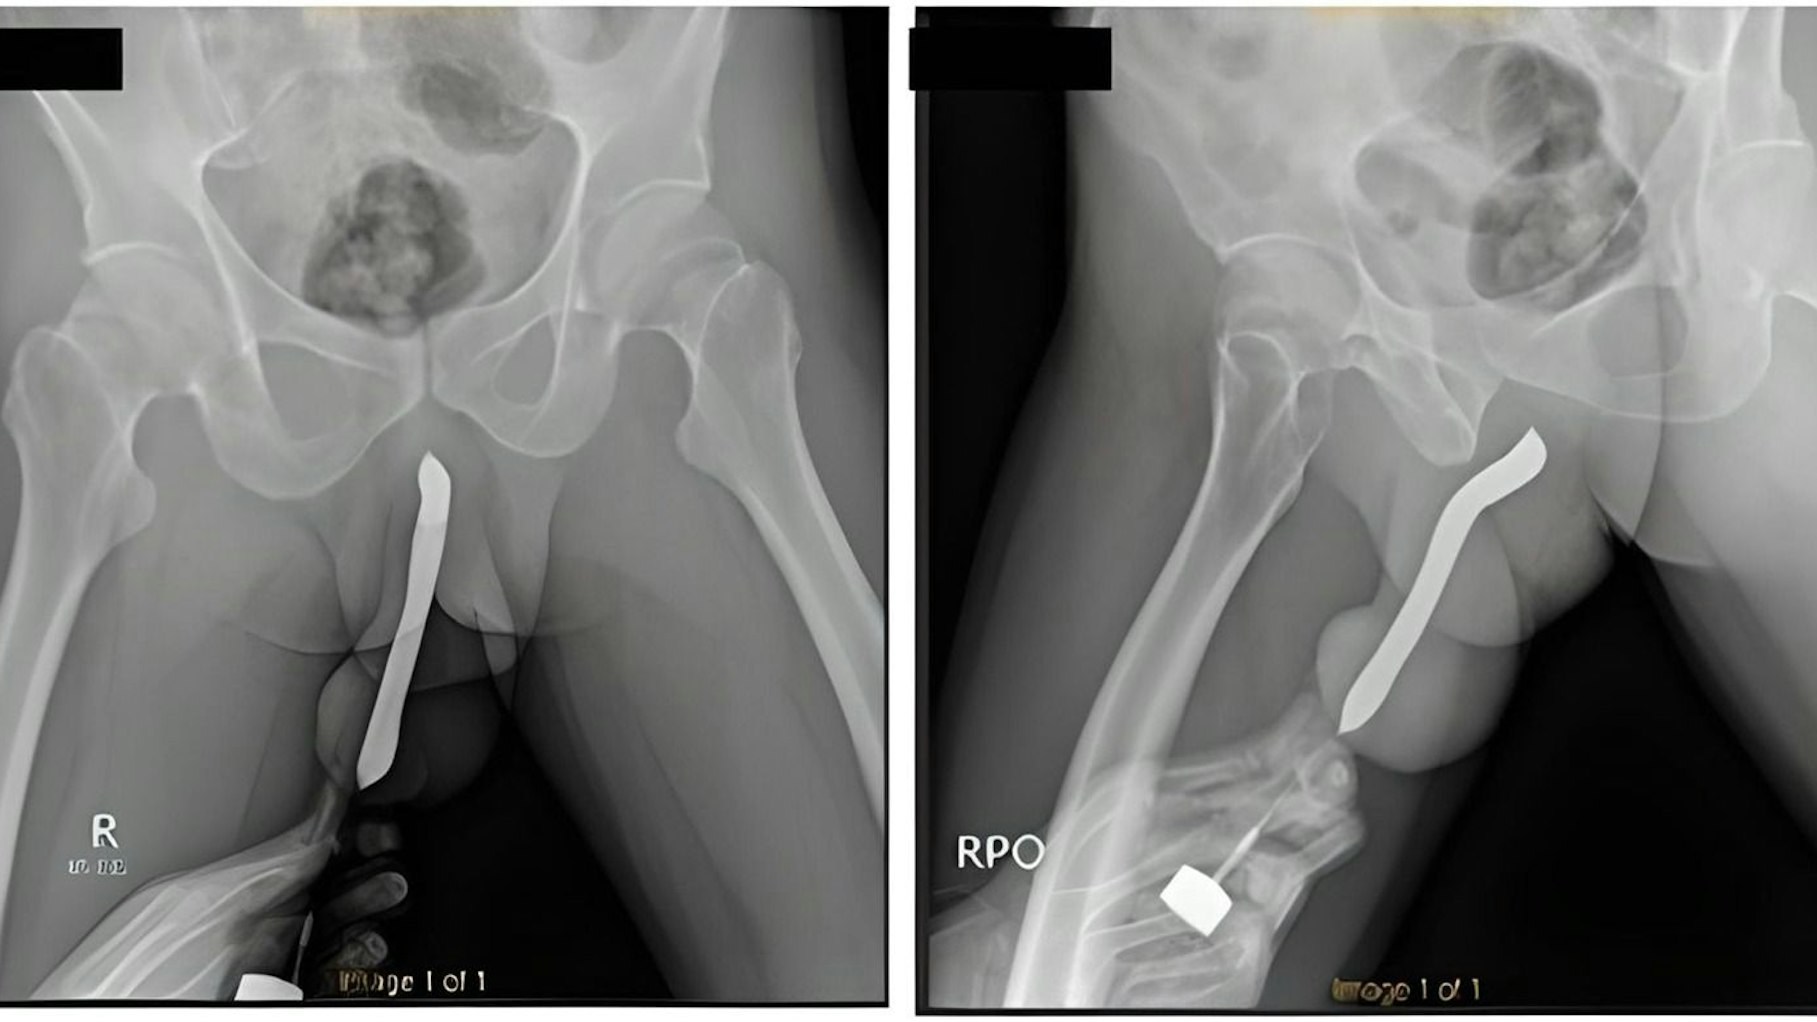

Copyright: International Journal of Surgery Case Reports/ScienceDirect

Ein 43-Jähriger aus Indonesien hatte sich für den Sex mit seiner Partnerin eine Zahnbürste in den Penis gesteckt. Die Bürste brach, es kam zur Penis-Ruptur.

Dann gestand der 43-Jährige: Er habe sich zur Luststeigerung einen Gegenstand in den Penis geschoben: eine handelsübliche Zahnbürste. Doch die ist während des Sex mit seiner Partnerin gebrochen – und mit ihr auch der Penis des unglücklichen Indonesiers.

Doch an jenem Tag ist diese Praxis ganz offensichtlich schiefgegangen: Beim Sex mit seiner Partnerin in der Missionarsstellung sei die Zahnbürste gebrochen – und der Penis wurde verletzt. Der hatte eine „Auberginenform“ – ein verräterisches Zeichen für einen sogenannten Penisbruch.

Ein weiteres Problem: Aus Scham wartete der Mann etwa 12 Stunden lang, bis er einen Arzt oder eine Ärztin aufsuchte. Die haben dann die Zahnbürste in einer zweistündigen Operation und entfernt und den Penis „repariert“.